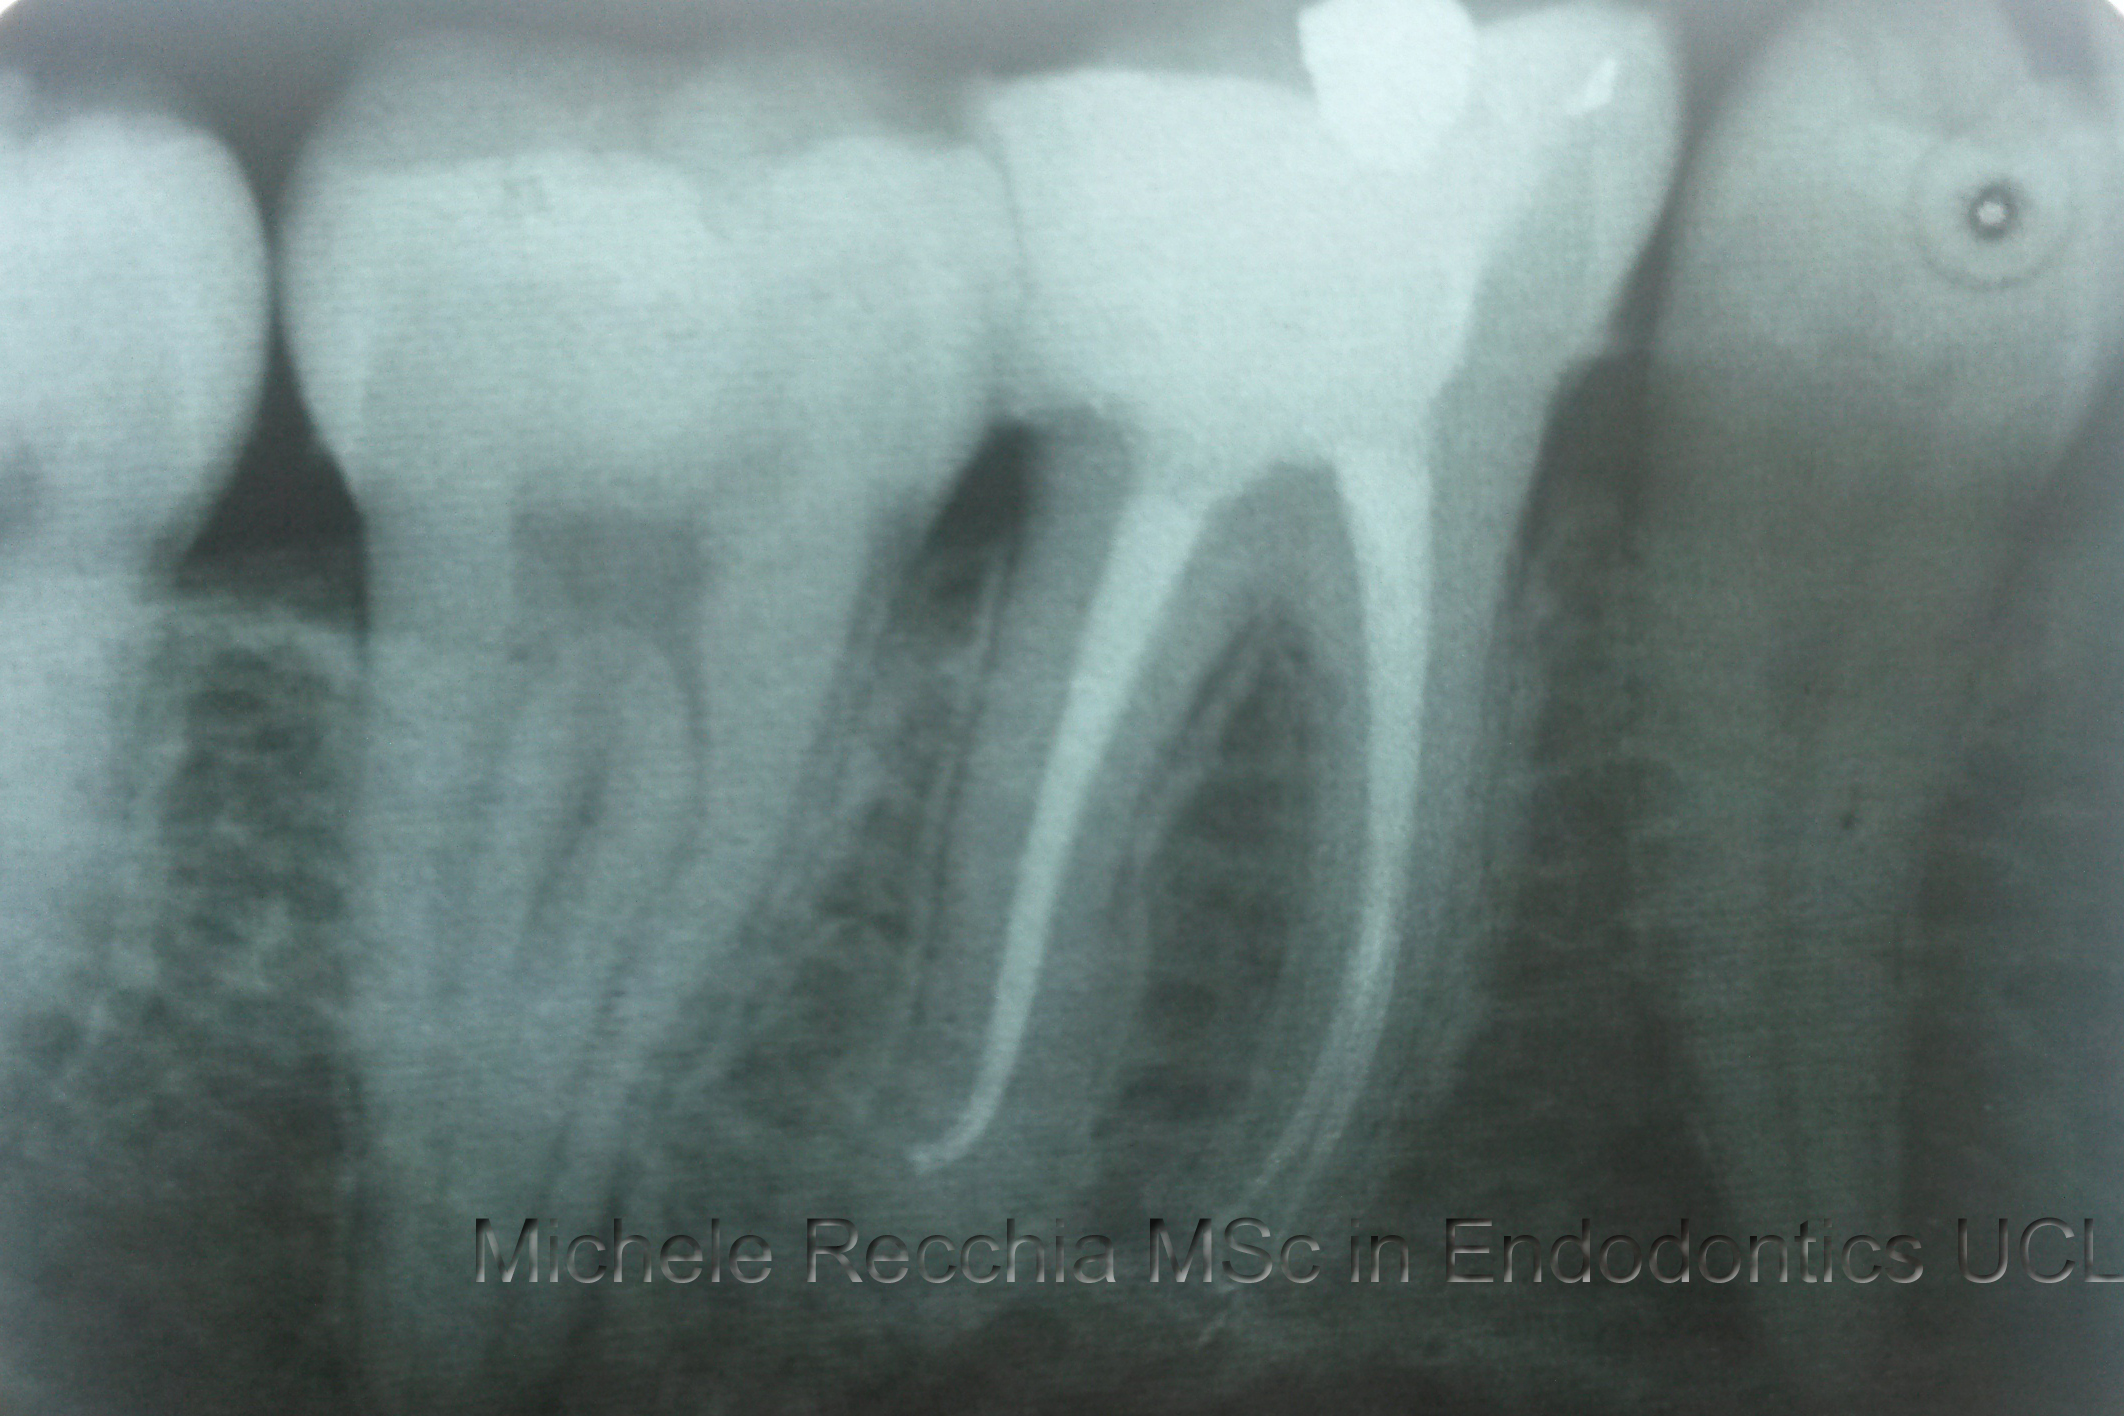

Root canal treatment is the process of going inside the pulp space and removing the infected dead tissue. The space is then disinfected and sealed with special materials.

After root canal treatment is complete, your restorative dentist will usually place a crown on your tooth to safeguard against fracture.